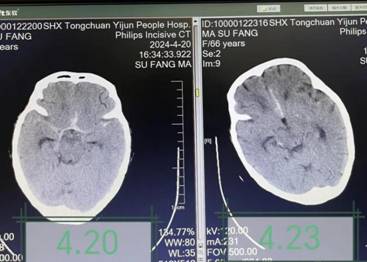

患者入院前2天蛛网膜下腔出血于西安某三甲医院神经外科ICU住院治疗,期间突然陷入深昏迷,且患者高龄、一般状况差、生命体征不稳定,主管医生告知家属患者病情极其危重,无手术机会,继续治疗意义不大。面对这一沉重打击,患者家属万念俱灰,放弃在西安继续治疗,转回宜君县人民医院拟行姑息治疗。了解病情后,医疗团队详细查阅患者病历资料,认真细致查体,患者生命体征不平稳,深昏迷状,疼痛刺激无反应,颈项强直。经讨论分析,患者突发昏迷的原因可能为再出血及脑血管痉挛,同时存在代谢性酸中毒、肺炎、电解质紊乱等影响脑功能,充分评估后,团队建议进行腰椎穿刺及脑脊液置换术。经与家属详细沟通,征得同意后连夜安排手术。手术由神经内科主治医师李妮妮操作,术中可见血性脑脊液流出,经多次脑脊液置换,脑脊液血色逐渐变淡,约半小时顺利结束手术。术后继续给予止血、营养神经、抗感染、纠酸、呼吸支持等综合治疗。在医护人员的精心照料下,次日查房患者意识转清,头痛症状明显缓解,能够与家属及医护人员正常交流,四肢活动也有明显恢复,复查颅脑CT显示出血及水肿情况较前减轻。经过3天巩固治疗,患者病情基本稳定。面对患者奇迹般的恢复,家属对治疗团队的敬业精神和高超医术表示惊叹及深深的感谢。

治疗前后颅脑CT对比,颅脑水肿及出血减轻